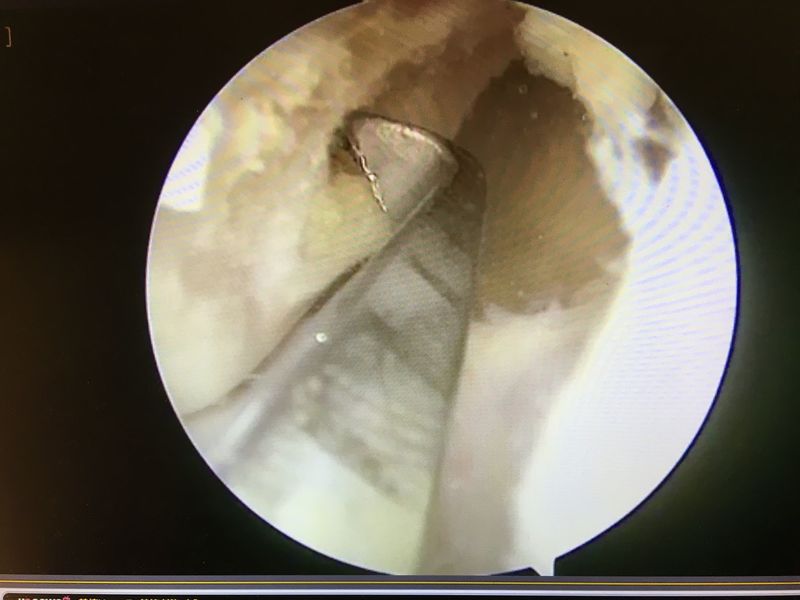

|

ACLは緊張がなく機能していない |

ACL再建

| 大腿骨孔作成 | グラフト挿入 | 再建靭帯 |